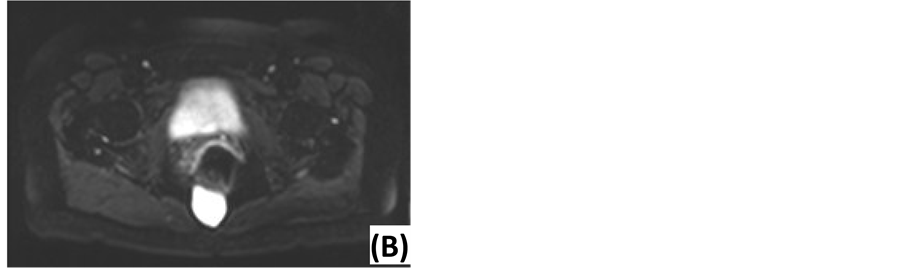

Preoperative work-up was done by MRI. Findings are summarized in Table 2 and propose a broad differential diagnosis. Examples are shown in Figure 2. Two diffusion-weighted MRI’s (DWI) were performed, using apparent diffusion coefficient (ADC) values at low (0 s/mm2) and high (1000 s/mm2) diffusion gradients. ADC values were high for both diffusion gradients (Figure 3). Five patients underwent computed tomography (CT) before MRI. Other technical investigations before MRI or CT included a positron emission tomography (PET), a transrectal ultrasonography (TRUS), a transabdominal ultrasonography and two anoscopies. No presacral lesions were found. TRUS illustrated dilated seminal vesicles. Transabdominal ultrasonography suggested acute appendicitis. One anoscopy revealed an anal fissure.

Figure 3. Diffusion-weighted MRI of an epidermoid cyst. (A) ADC map: low signal intensity. (B) DWI with low diffusion gradient (b = 0 s/mm2): high ADC value. (C) DWI with high diffusion gradient (b = 1000 s/mm2): high ADC value.

Due to the excellent soft-tissue resolution and multiplanar capacity, MRI is the best imaging modality to assess tumor location, size, morphology and adjacent structures [5] [6] [10] . The risk of malignancy can be estimated based on following features: heterogeneity, solid appearance, irregular or infiltrative borders, variable enhancement after gadolinium administration, rapid growth and extension above S3 [3] [5] [18] . Our findings predicted malignancy with 100% accuracy, confirming the current literature. Biological behavior also correlates with diffusion restriction. DWI can distinguish benign and malignant lesions, using quantitative ADC measurements. Several authors report significantly higher ADC values at high diffusion gradients for benign lesions [31] -[33] . Our findings concur with this conclusion. Specific diagnosis by MRI is difficult. Glasgow et al. report 28% of MRI diagnoses to be in accordance with the histological diagnosis [2] . Radiological evaluation provided a differential diagnosis in order of preference. Accuracy was 57.1%: two epidermoid cysts were mistaken for tailgut cysts and one tailgut cyst was mistaken for endometriosis. Presacral cysts usually have low signal intensity on T1-weighted images and high signal intensity on T2-weighted images. This may be influenced by the cyst’s content: blood, proteins and mucins cause higher signal intensity on T1-weighted images. Fat content is best seen on T1-weighted images using fat suppression. This is suggestive of a dermoid cyst. Tailgut cysts are multicystic, in contrast to other cystic masses. A chordoma is lobulated with a heterogeneous high signal intensity on T2-weighted images and low-intermediate signal intensity on T1-weighted images. Gadolinium injection reveals a heterogeneous enhancement with a honeycomb appearance [5] [18] [34] .